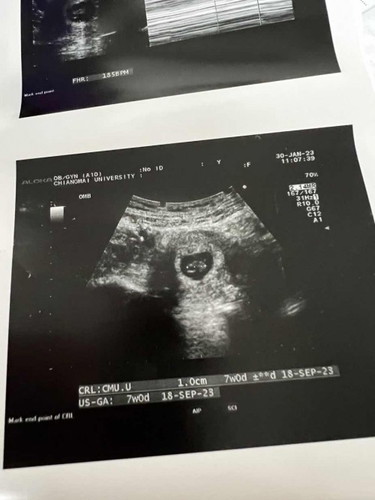

ภาวะแท้งคุกคาม 7สัปดาห์

วันนี้มีเลือดสีน้ำตาลอ่อน ออก ไปหาหมอหมอตรวจภายในปรากฎว่าเลือดสีแดงสดออกมาเยอะมากก เป็นภาวะแท้งคุกคาม ตอน 7สัปดาห์ พอหมออัลตราซาวด์ดูหัวใจเด็กเต้นปกติ ใครดูอัลตราซาวด์ออกบ้างคะเหลือน้อยลอยในน้ำคล่ำแบบนี้ปกติใช่ไหมคะ ขอวีธีการดูแลตัวเองหน่อยคะ 💕💕 ท้องแรก#ขอบคุณสำหรับคำตอบค่ะ